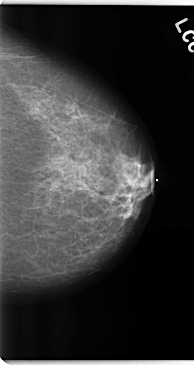

C_0225_1.LEFT_CC

LEFT_CC LINES 4744 PIXELS_PER_LINE 2512 BITS_PER_PIXEL 12 RESOLUTION 50 NON_OVERLAY